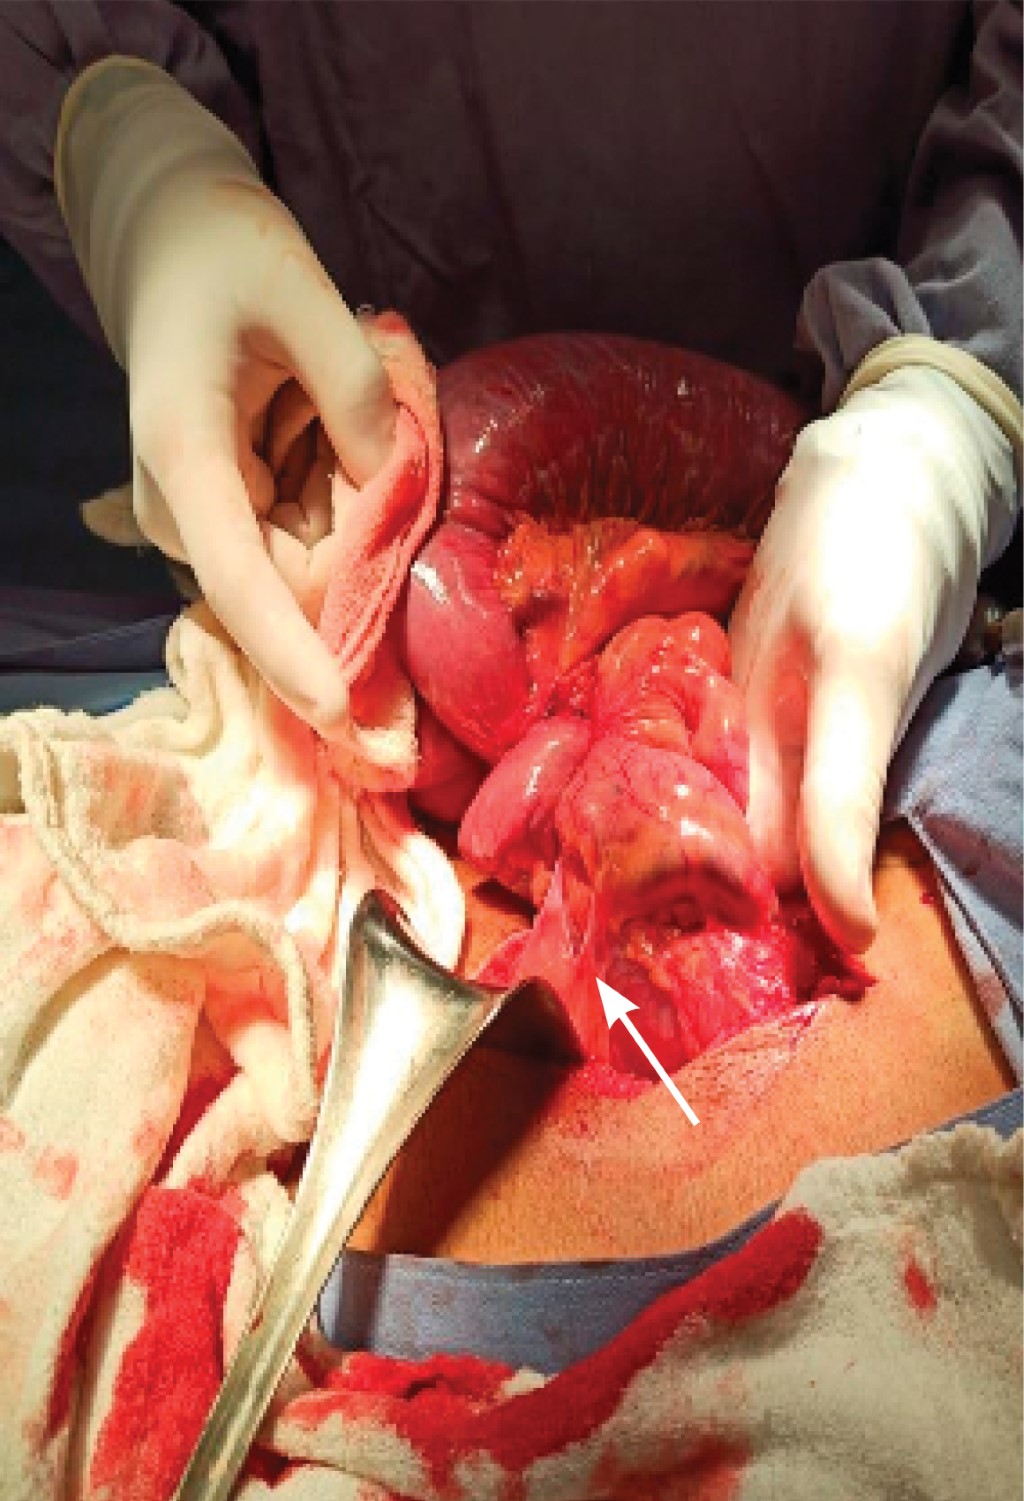

Due to the poor response to conservative medical management for 24 hours, with the placement of a nasogastric tube and given the impossibility of having a complementary study such as a CT scan of the abdomen, it was decided to go to the operating room to perform an exploratory laparotomy. The preoperative diagnosis was high intestinal occlusion. On surgery, there were findings of intestinal occlusion by extrinsic duodenal compression and incomplete intestinal rotation, with the duodenum located to the right of the midline, Ladd peritoneal bands (Figure 3), significant duodenal dilatation (Figure 4), and an incomplete fixation of the hepatic angle of the colon in abnormal position. The presence of partial stenosis of jejunum at 15, 25, and 35 cm from the duodenum, two varicose veins of 1.5 cm in diameter, which run along the mesenteric border of the jejunum for approximately 150 cm (Figure 5), the jejunum with atrophy in its first 100 cm, and the hepatic angle of the colon located to the right of the midline were identified.

However, despite the lysis of adhesions, the cecum remains in a spiral form without the possibility of fixing it adequately, so a right hemicolectomy with manual anterolateral intertransverse anastomosis was performed. First, the ends of the transverse colon and ileum were closed in two planes: the first with polyglactin 2-0 simple suture, and the second plane was closed with separate Lembert stitches with 2-0 silk. Next, the anastomosis was performed in two planes, the first with polyglactin 2-0 single suture stitches on the posterior aspect of the anastomosis and a Connell Mayo stitch on the anterior aspect; and the second plane was closed with separate invaginating Lembert stitches with 2-0 silk.

However, in this reported case, and despite performing the maneuvers described above, the patient continued to have the ascending colon and terminal ileum in a spiral form without the possibility of an adequate and safe fixation; to avoid the possibility of intestinal torsion and subsequent necrosis, the decision was made to perform a right hemicolectomy with intertransverse anterolateral anastomosis, which resulted in a satisfactory evolution during his hospital stay and up to the present time.

Figure 3